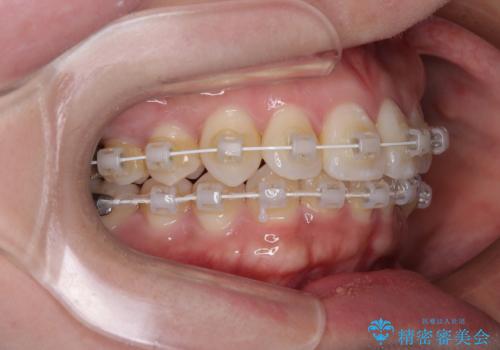

矯正中の見た目にも配慮し、プラスチックブラケット+コーティングワイヤーの目立ちにくい審美装置を採用しました。

- 審美装置

- 1年3ヶ月

- 10-30回